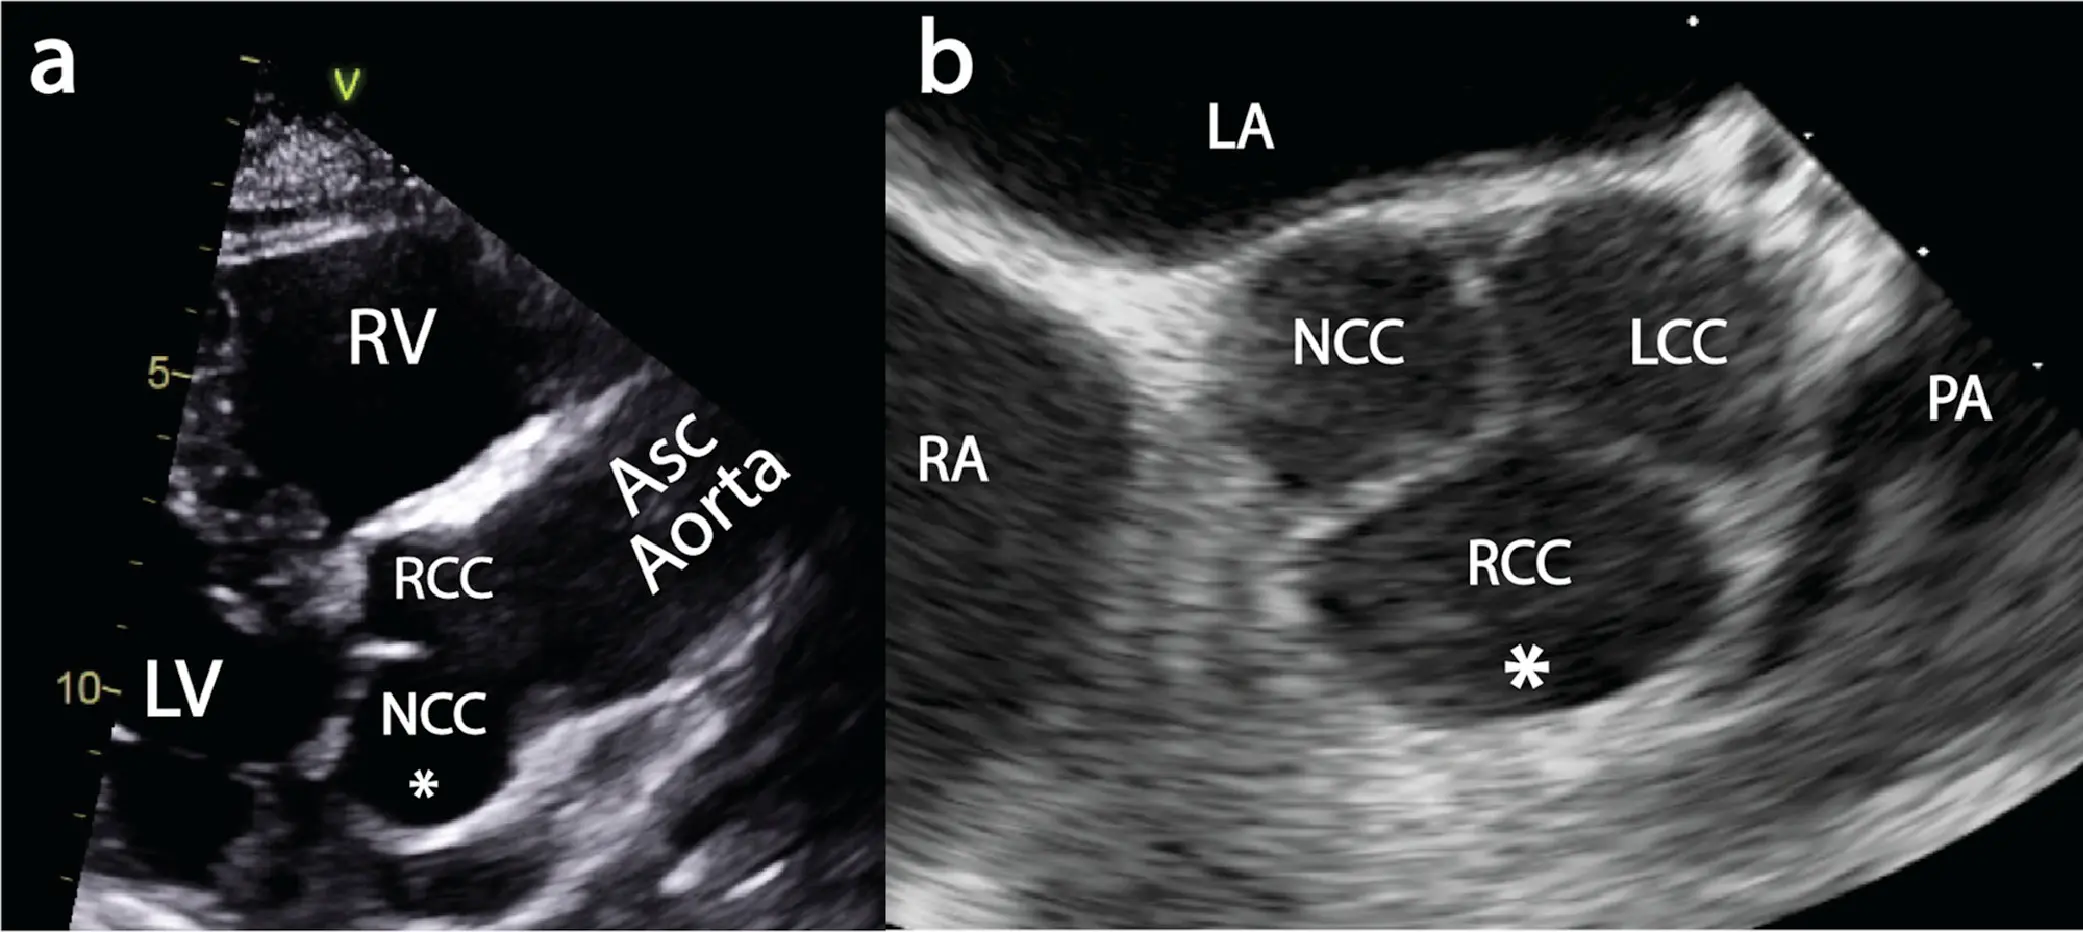

- The aortic root is an extension of the LVOT, extending from the basal attachment of the aortic valve cusps within the LVOT to their peripheral attachment at the level of the sinotubular junction. Its components are the sinuses of Valsalva, the fibrous interleaflet triangles and the valvular cusps themselves.

- not a true or distinct anatomic structure but is a virtual ring that may be defined by joining the basal attachments, or nadirs, of the three aortic leaflets. The distal (uppermost) attachments of the leaflets, in the shape of a crown, form a true anatomic ring.

- The aortic annulus is defined as the luminal contour within a virtual plane aligned with the most basal attachment points of the three aortic valve cusps (sometimes referred to as the ‘basal hinge points’).

- Quantitative assessment requires the accurate identification of each of these three points in turn to create a plane that transects all three.